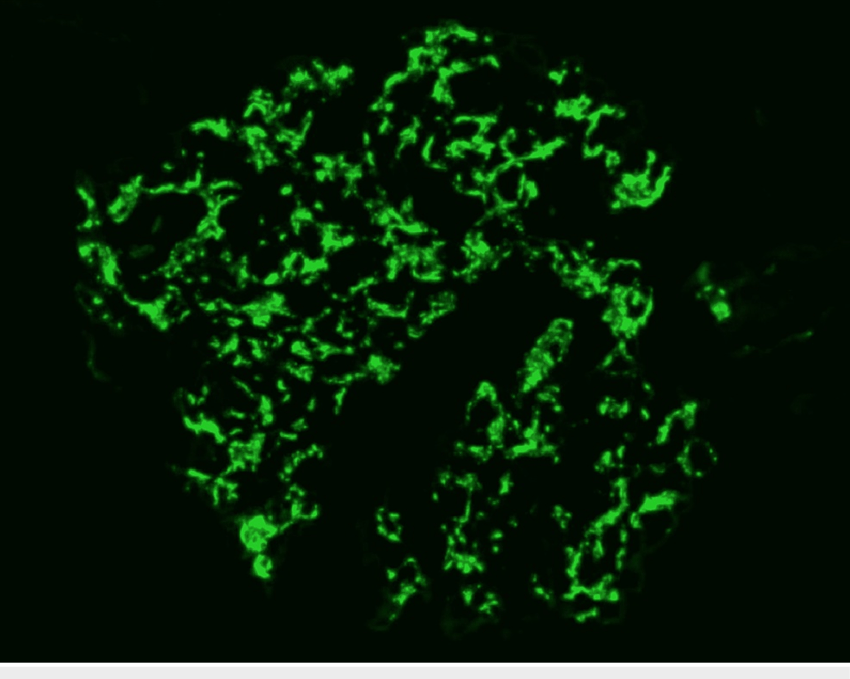

A alta da IRA realmente significa recuperação… ou apenas o começo da DRC futura? Albuminúria, reintrodução de IECA/BRA, iSGLT2 e seguimento precoce podem mudar completamente o prognóstico pós-IRA — e muita gente ainda foca só na creatinina da alta. Esse artigo do Clinical Kidney Journal traz 10 pontos práticos que todo nefrologista deveria revisar no seguimento pós-IRA.